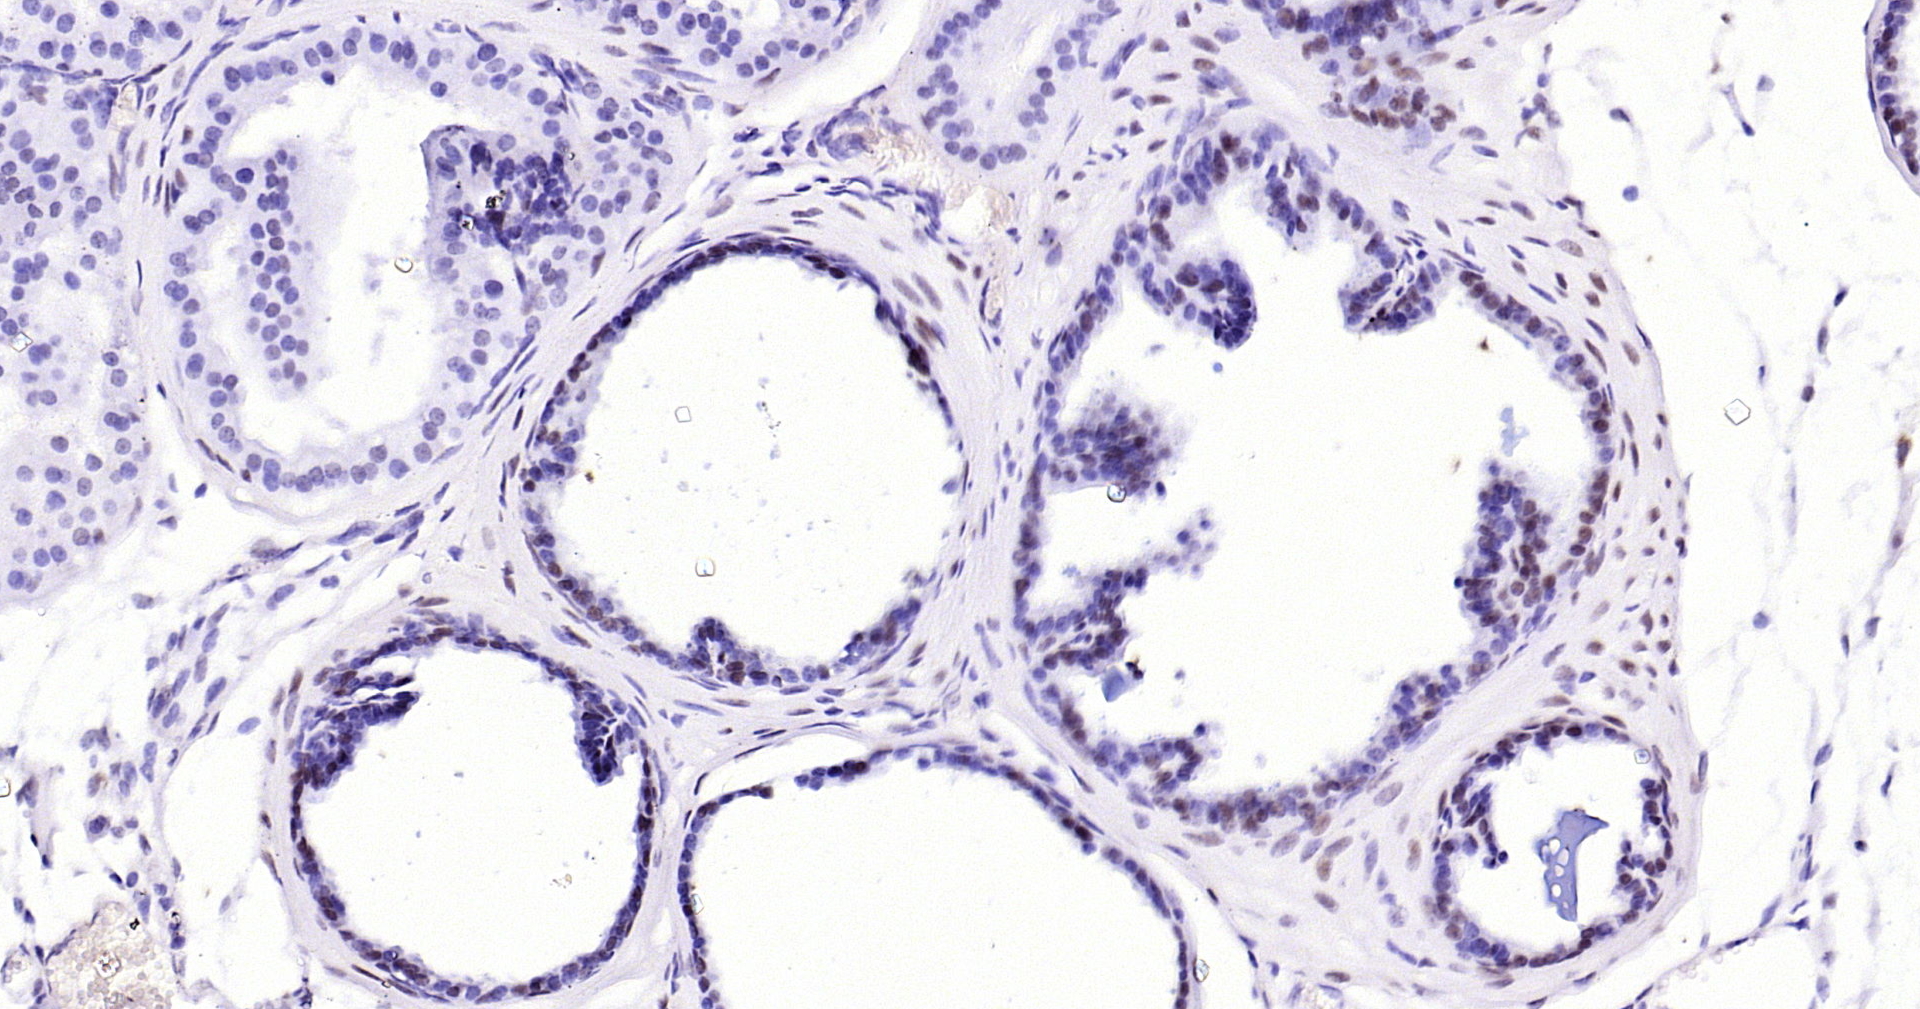

Androgen receptor Recombinant Antibody

• IHC-P

Product Name Androgen receptor Recombinant Antibody

Applications WB, IHC-P, IHC-F, IF(IHC-P)

IHC-P IHC-P1:50-200